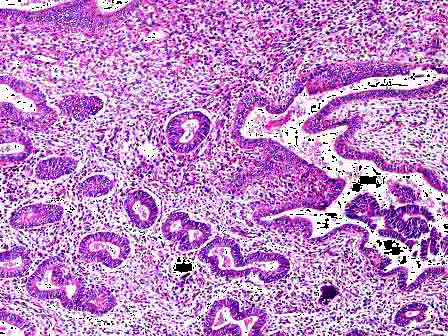

问题 女性,46岁,阴道不规则出血1年,诊刮子宫内膜,显微镜下见腺体增生密集,与间质比>3:1,腺体呈乳头状,可见背靠背现象,伴嗜酸性粒细胞浸润,腺上皮异型性并见核仁(如图),应诊断为 ( )

选项 A.子宫内膜单纯性增生 B.子宫内膜复杂性增生 C.子宫内膜单纯性增生伴非典型增生 D.子宫内膜复杂性增生伴非典型增生 E.子宫内膜腺癌

答案 C